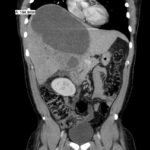

Although rare in the developed world, amebic infections are common worldwide and represent a challenging and often overlooked diagnosis. In this case, an amebic liver abscess was discovered in a 29-year-old male who presented to the emergency department (ED) complaining of right upper quadrant abdominal pain, weight loss, non-bilious/non-bloody vomiting, and diarrhea for three months. He recently traveled to India and Mexico. Point-of-care ultrasound discovered a liver mass and computed tomography (CT) confirmed the presence of a liver abscess. The case highlights the usefulness of ultrasound as an initial diagnostic tool, the importance of careful travel history in patients with suspected infectious diseases, and the initial provision of broad-spectrum coverage for bacterial and amebic pathogens for liver abscesses until the pathogen has been identified.